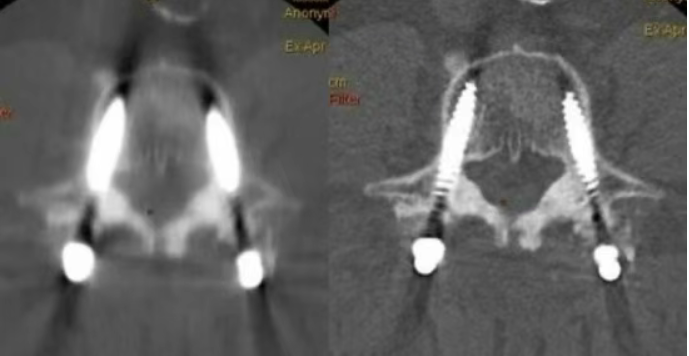

金属伪影消除:优化术后评估

对于金属植入术后患者,综合能谱成像与MARs技术,有效减除金属伪影,清晰呈现周围组织,为骨折内固定、关节置换等术后复查、随访,提供高质量图像,辅助医生精准评估恢复情况。